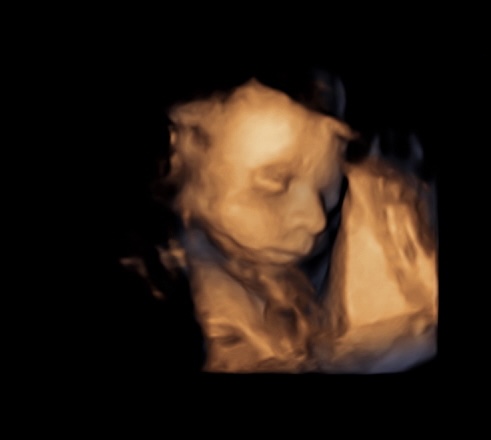

3D/4D ultrazvuk - tvárička drobca

Ahojte, kedy ste boli na 3D/4D ultrazvuku ? V ktorom TT ? Aby už pekne bola vidieť tvárička drobca ?

Ďakujem baby , nakoniec som si zavolala doktorovy a objednal ma na 26tt , vraj to je ideál že bude pekná babatkovska tvárička 😁 som zvedavá a už sa zas neviem dockat a budem škrkat v kalendári 💙😂🙋🏽♀️

@ki_ki2 ja prvy krat okolo 20tt to uz bola peknučkaa a potom okolo 28tt ale to uz bola moc velka tak sa schovavala